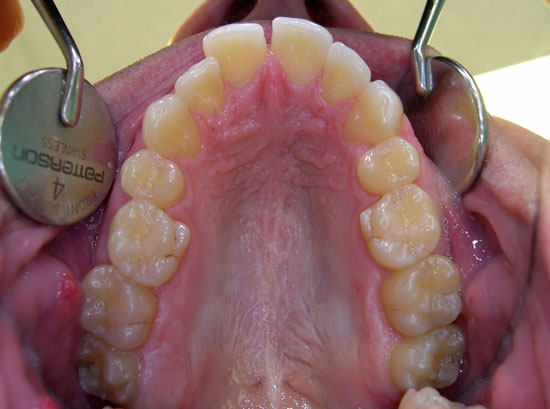

Case 2 - Upper Teeth Before

Case 2 - Upper Teeth After